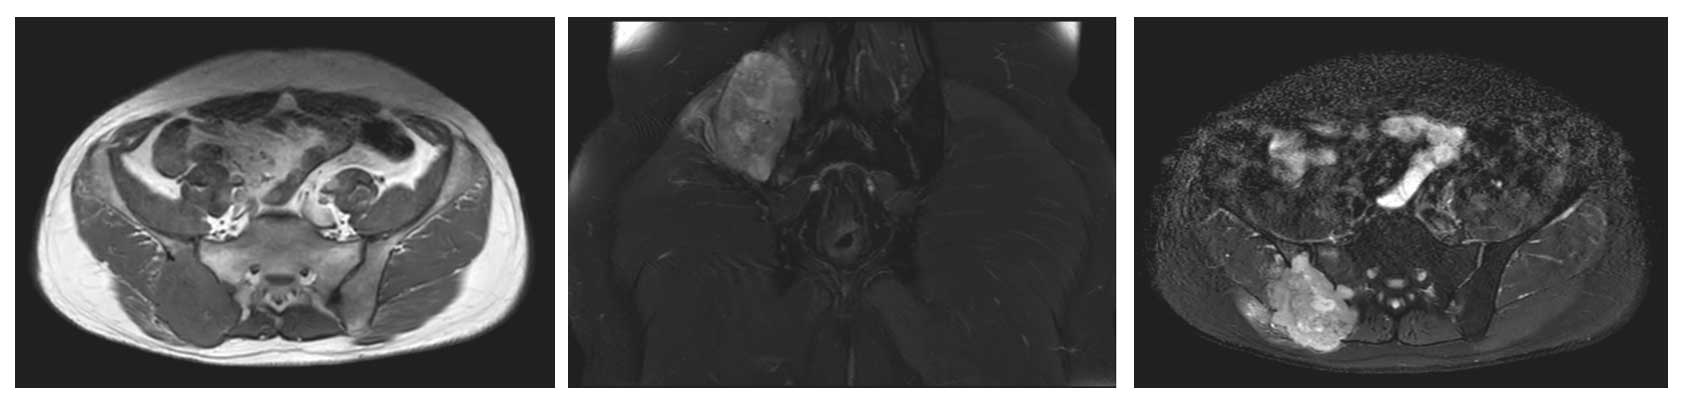

Ameliyat Öncesi: MR’da aynı lokalizasyonda düzensiz sınırlı, yumuşak dokuya uzanım gösteren tümör dokusu görülmekte.